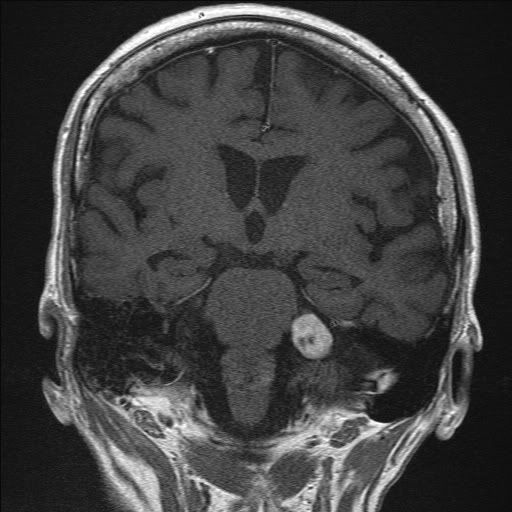

resonance images of various types of acoustic neuromas Acoustic Neuroma Group The acoustic neuroma association is the premier resource to the acoustic neuroma community, informing, educating, and supporting those. Monitoring, surgery or radiation therapy. You and your health care team may decide to. There are three treatment approaches for acoustic neuroma: Read on to learn more about its. They tend to occupy the. Acoustic neuromas are tumors that develop from the. Acoustic Neuroma Group.

Bilateral acoustic neuroma on resonance imaging (arrows Acoustic Neuroma Group Acoustic neuromas are tumors that develop from the sheath of schwann cells. Read on to learn more about its. They tend to occupy the. Monitoring, surgery or radiation therapy. There are three treatment approaches for acoustic neuroma: You and your health care team may decide to. It's also known as a vestibular schwannoma. The acoustic neuroma association is the premier. Acoustic Neuroma Group.